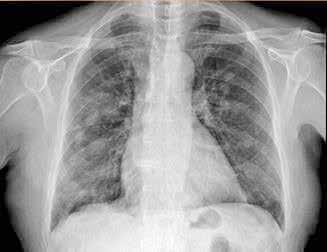

Se revisaron las pruebas solicitadas en Urgencias. En la analítica se en contró una hemoglobina (Hb) de 14 g/dl, un volumen corpuscular medio (VCM) elevado (106μ³) compatible con su historia de alcoholismo o con un déficit de ácido fólico o vitamina B12, una discreta elevación de la proteina C reactiva (13,2 mg/dl) sin elevación de otros reactantes de fase aguda y unas enzimas hepáticas dentro de la normalidad, con la aspartato transfe rasa ligeramente elevada 39 U/L (rango de normalidad: 5-34). Los tóxicos en orina fueron negativos, así como la etanolemia. La radiografía (rx) de tórax mostraba una condensación en el lóbulo superior izquierdo en posi ble relación con la infección tuberculosa diagnosticada en 2011 (Figura 1). La TC -a pesar de no mostrar signos de patología aguda intracraneal, ni masas ni signos de sangrado- sí que mostraba atrofia cerebral con surcos muy marcados, hallazgo no concordante con la edad de nuestro paciente (Imagen 2).

Figura 1. Radiografía de tórax en bipedestación AP y Lat.

Lesiones residuales/cicatriciales en campo superior izquierda, con aumento de densidad de parénquima, bronquictasias y pérdida de volumen, en relación con antecedente de TBC. Parénquima pulmonar derecho aceptablemente ventilado. Siluesta cardiovascular normal.